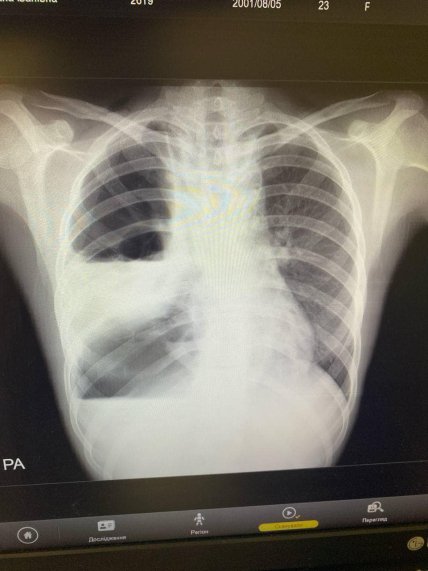

Рентген-снимок пациента на 2-й день после операции

"Врачами отделение одномоментно выполнено цервикотомию с левой стороны, правостороннюю торакотомию с медиастинотомией, верхне-серединную лапаротомию, гастротомию с наложением гастростомы", — добавили медики.